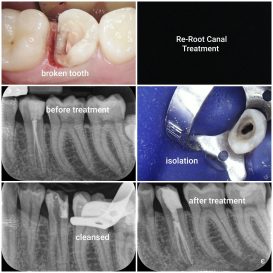

CBCT imaging is particularly valuable for procedures such as dental implants, oral surgery, endodontics, orthodontic assessment, and complex diagnostic cases, where accuracy is essential.